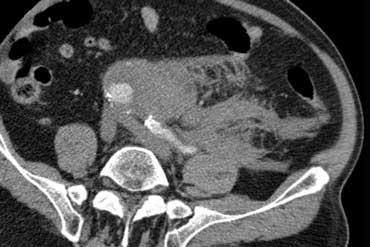

Viêm túi thừa sigma không biến chứng. Dấu hiệu mờ mỡ và dày thành đại tràng khu trú tại vùng có túi thừa. Không có hình thành áp xe.

Các biến chứng của viêm túi thừa như hình thành áp xe hoặc thủng, có thể được loại trừ tốt nhất bằng CT.

TRÁI: Viêm túi thừa sigma. Túi thừa (mũi tên) được bao quanh bởi lớp mỡ tăng tỷ trọng. Thành sigma dày. PHẢI: Ung thư sigma với dấu hiệu mờ mỡ giới hạn.

Một bẫy chẩn đoán quan trọng là ung thư đại tràng, có thể biểu hiện với các đặc điểm hình ảnh tương tự, đặc biệt khi ung thư đại tràng được bao quanh bởi dấu hiệu mờ mỡ do xâm lấn, phản ứng xơ hóa (desmoplastic reaction) hoặc viêm.

Thường không thể phân biệt một cách đáng tin cậy giữa viêm túi thừa và ung thư đại tràng, do đó chúng tôi thường xuyên đưa ung thư đại tràng vào chẩn đoán phân biệt của viêm túi thừa sigma.